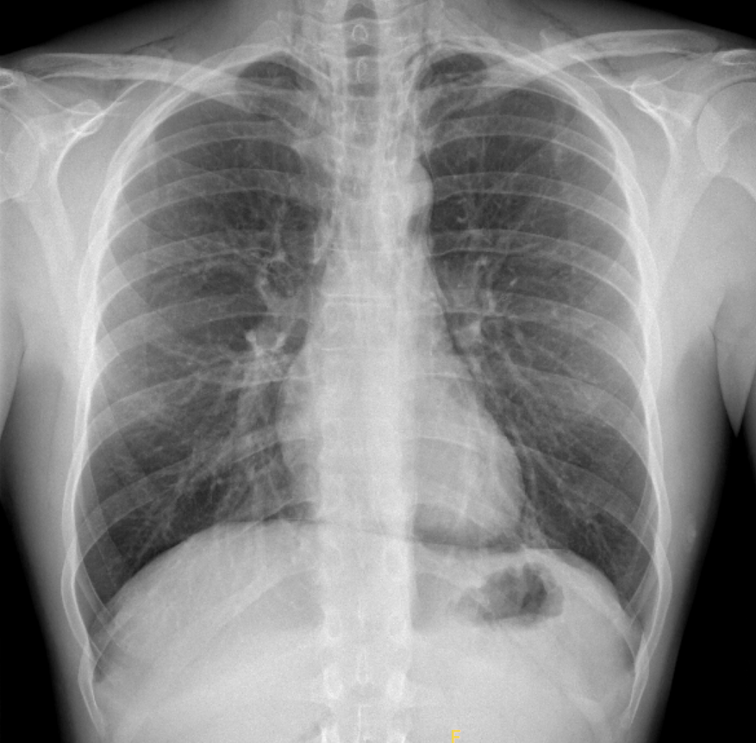

Un jeune patient se présente pour une douleur thoracique respiro-dépendante associé à une dyspnée. A la radiographie du thorax un pneumomédiastin (PM) est diagnostiqué. Le scanner thoracique révèle un PM se propageant jusque dans les parties molles du cou, sans lésion sous-jacente mise en évidence. Le bilan ORL et gastroscopie est dans la norme. La bronchoscopie met en évidence une possible lésion de la bronche souche gauche proximale, traitée conservativement.

Le diagnostic se fait avec une radiographie de thorax standard. Les examens complémentaires tels que scanner thoracique, la bronchoscopie, l’ODG sont nécessaires pour identifier ou exclure une étiologie primaire.